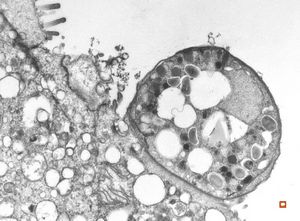

M,46y. | Entamoeba histolytica